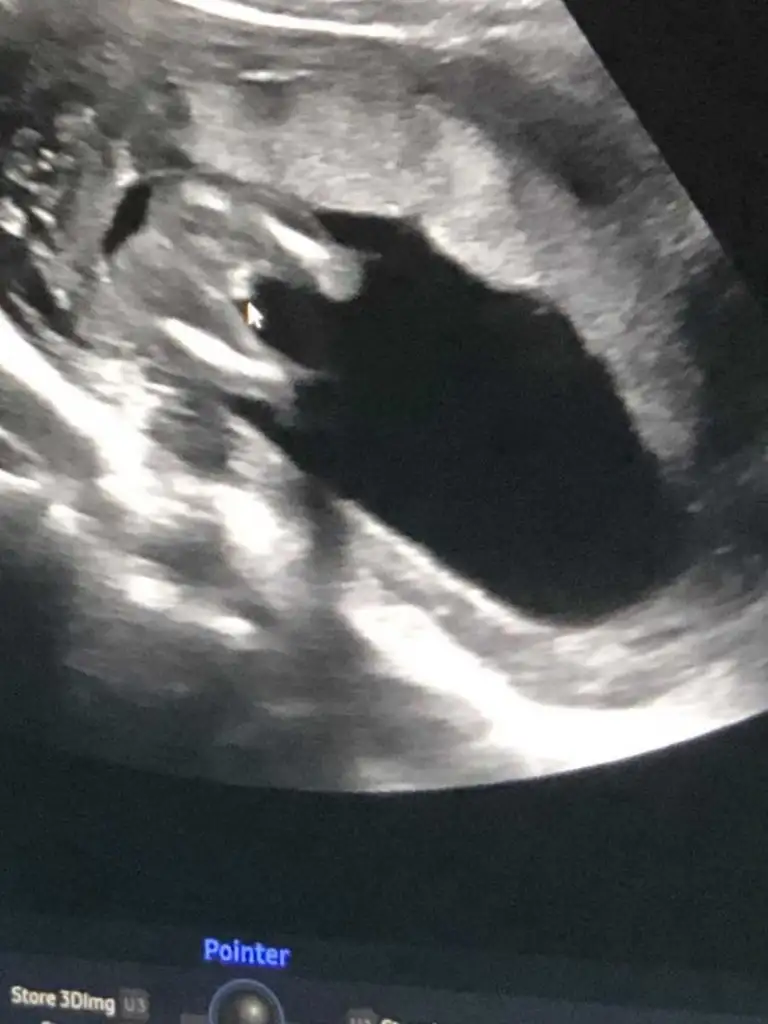

Çok uzun olmuş ama benim ki ne ozaman

• 6F250A3F-67FD-4626-8912-CDBFD8EB0955.webp

6F250A3F-67FD-4626-8912-CDBFD8EB0955.webp

25,8 KB · Görüntüleme: 301

• 3C1994AC-8CDA-47A2-9B5A-6E512B9204E4.webp

3C1994AC-8CDA-47A2-9B5A-6E512B9204E4.webp

25,5 KB · Görüntüleme: 293